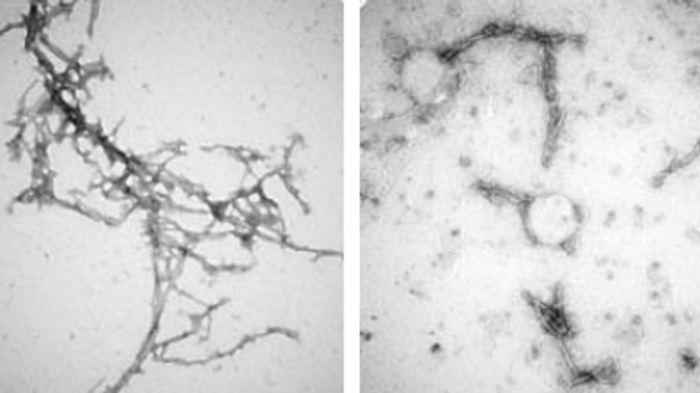

image: The structure of alpha-synuclein clumps (on the left) was disrupted by the nanobody PFFNB2 (as shown on the right). view more

Additional tests in mice showed that the PFFNB2 nanobody cannot prevent alpha-synuclein from collecting into clumps, but it can disrupt and destabilize the structure of existing clumps.